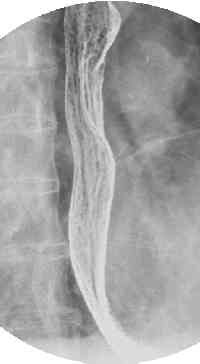

The oldest test was a barium swallow or upper GI exam. Also useful is a CT scan (CT #2) , and normal CT#3, and CT#4, through the chest and cross sectional anatomy here and here.